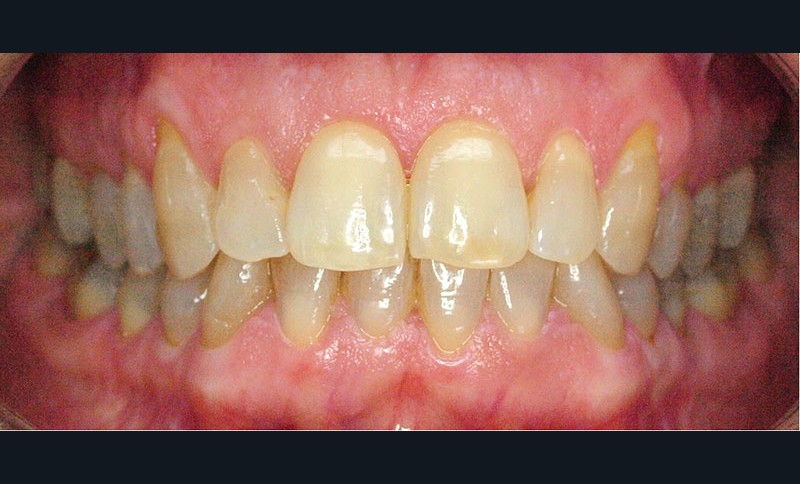

Voilà 6 mois, une patiente se présente à notre cabinet au motif d’une douleur récurrente sur le secteur molaire supérieur droit lors de la mastication. Une anamnèse rapide et cadrée est réalisée pour optimiser le temps passé et avancer les éléments diagnostiques. La patiente décrit une gêne ancienne, déclenchée essentiellement par la mastication. À l’auscultation, les examens endo-buccaux et radiologiques montrent une denture superbe avec très peu de soins, une hygiène buccale sans reproche, et des fonctions manducatrices saines [1] (fig. 1 et 2).